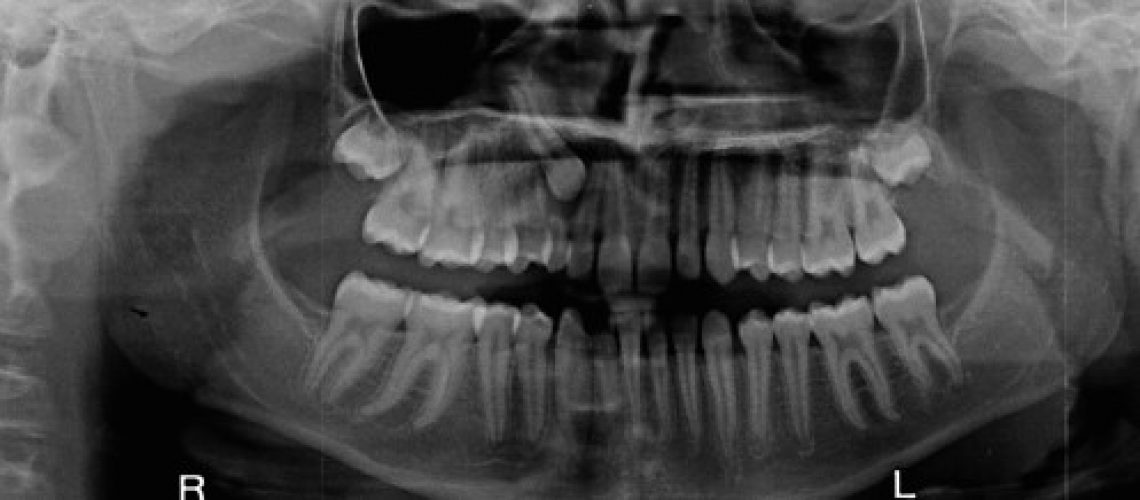

When we take an x-ray, it’s because there’s a health benefit we can’t provide without it. Dental x-rays enable us to diagnose orthodontic problems and potential other dental health issues that need attention. Left unattended, these dental health issues could cause bigger health problems that far outweigh potential exposure to the relatively low amount of radiation from our digital x-ray technology.